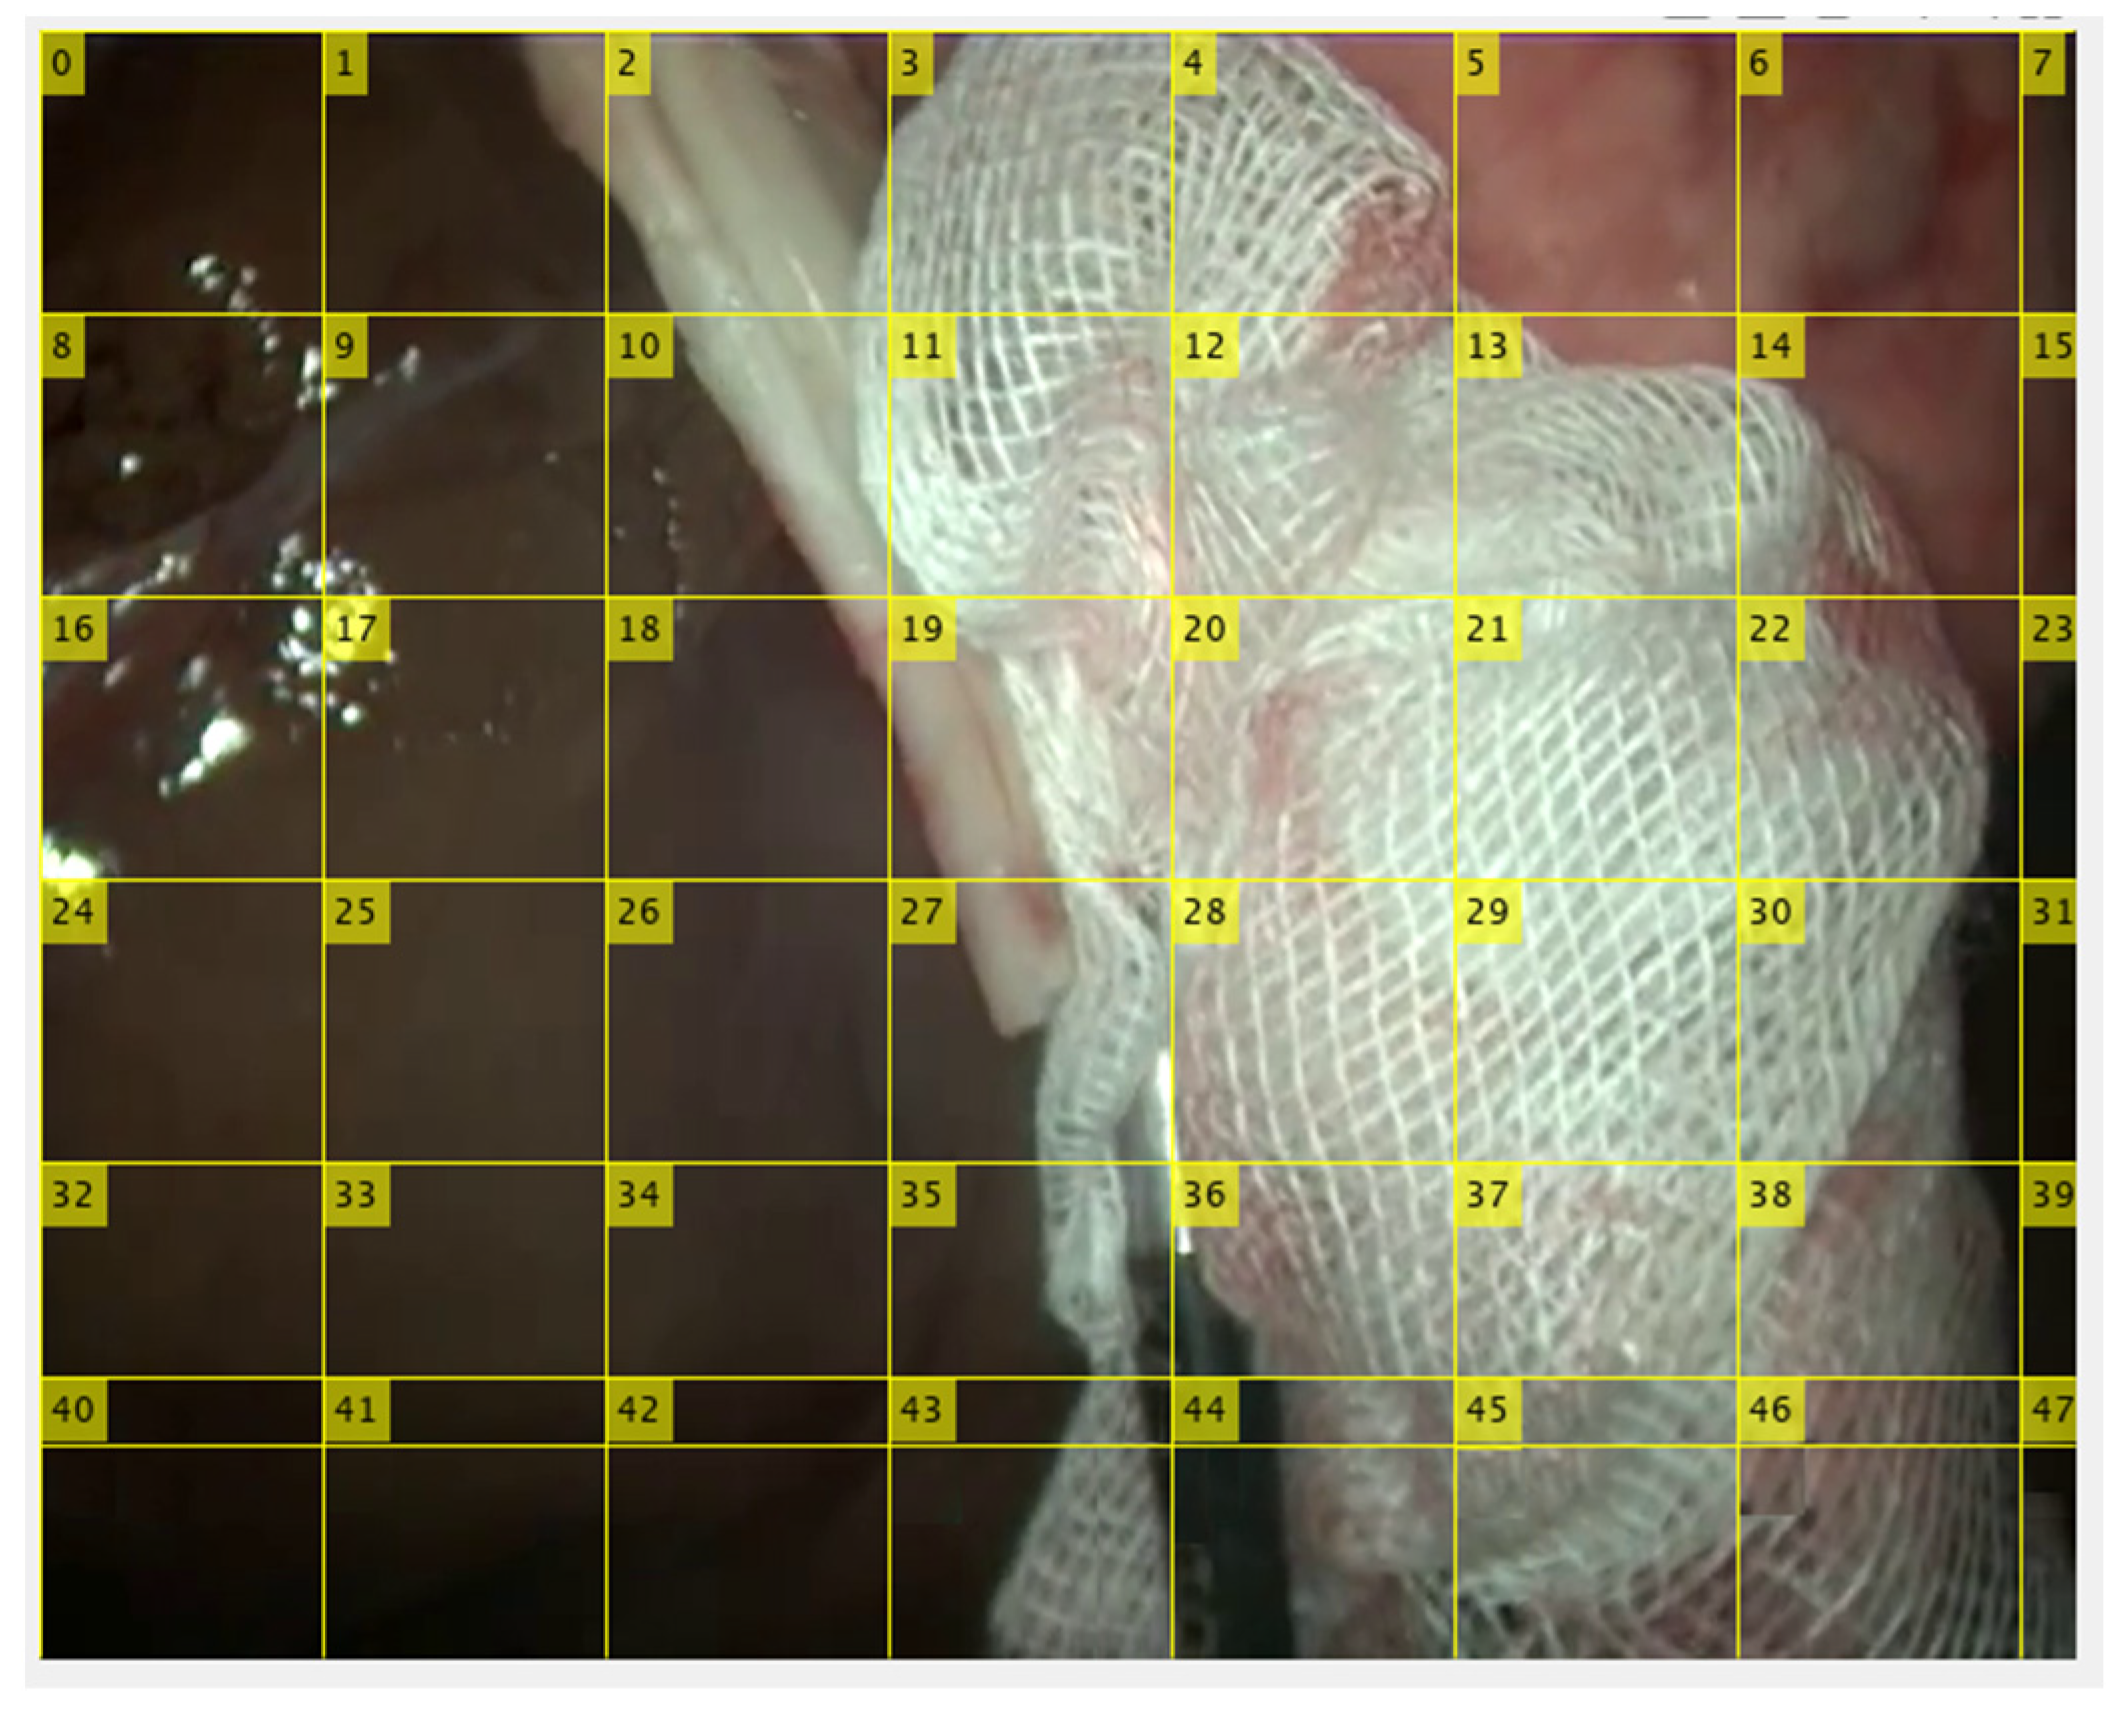

2.4. Gauze Coarse Segmentation

3.2. Gauze Coarse Segmentation